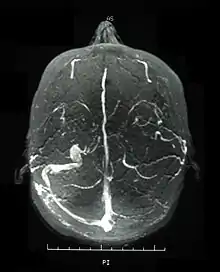

Central nervous system (CNS) involvement most often occurs as a chronic meningoencephalitis. Lesions tend to occur in the brainstem, the basal ganglia and deep hemispheric white matter and may resemble those of multiple sclerosis (MS). Brainstem atrophy is seen in chronic cases.

Neurological involvements range from aseptic meningitis to vascular thrombosis such as dural sinus thrombosis and organic brain syndrome manifesting with confusion, seizures, and memory loss. Sudden hearing loss (sensorineural) is often associated with it.[4] They often appear late in the progression of the disease but are associated with a poor prognosis.

Visual acuity, or color vision loss with concurrent mucocutaneous lesions or systemic Behçet's disease symptoms should raise suspicion of optic nerve involvement in Behçet's disease and prompt a work-up for Behçet's disease if not previously diagnosed in addition to an ocular work-up. Diagnosis of Behçet's disease is based on clinical findings including oral and genital ulcers, skin lesions such as erythema nodosum, acne, or folliculitis, ocular inflammatory findings and a pathergy reaction. Inflammatory markers such ESR, and CRP may be elevated. A complete ophthalmic examination may include a slit lamp examination, optical coherence tomography to detect nerve loss, visual field examinations, fundoscopic examination to assess optic disc atrophy and retinal disease, fundoscopic angiography, and visual evoked potentials, which may demonstrate increased latency. Optic nerve enhancement may be identified on Magnetic Resonance Imaging (MRI) in some patients with acute optic neuropathy. However, a normal study does not rule out optic neuropathy. Cerebrospinal fluid (CSF) analysis may demonstrate elevated protein level with or without pleocytosis. Imaging including angiography may be indicated to identify dural venous sinus thrombosis as a cause of intracranial hypertension and optic atrophy.